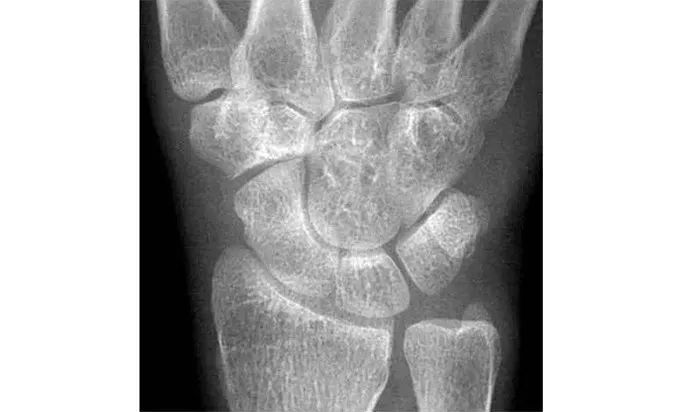

Case 分析

舟骨-大多角骨-小多角骨关节(STT关节)、第1腕掌关节(CMC1关节)严重骨关节病伴半脱位,掌骨弧线正常、平行关系存在。舟骨变长提示其向背侧倾斜。

侧位片示月骨也向背侧倾斜,近排腕骨作为一个整体移动,所以不存在脱位。

最后诊断:无脱位DISI(背屈不稳)伴STT关节骨关节病及半脱位。